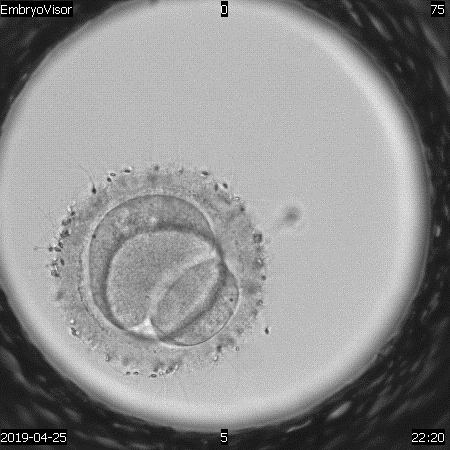

During the analysis of video files, we can state signs of normal -2PN2PB or abnormal fertilization (3PN) (Fig. 1, 2). The second feature is reverse crushing. If it is detected in the development of the embryo, this reduces its chances of implantation in the presence of others in which we have not recorded this feature (Fig. 3). The presented series of images show a series of frames that show the dynamics of the development of this process. In the first case, the embryo, which began division from the three-cell stage, goes through the stage of reverse cleavage into the two-cell stage. The appearance of multinucleation (several nuclei in developing blastomeres) is also a reason to exclude embryos for transfer and cryopreservation if other embryos of comparable quality are available.

Monitoring the process of embryo development makes it possible to fix various stages of morphokinetic transformations, to establish the presence of cytoplasmic and extracytoplasmic structuresmultinucleation, fragmentation, vacuolization, etc., and also to evaluate their contribution to the early development of embryos [15,16]. At present, it is extremely important to identify the predictors of the development of a competent embryo, which determine its implantation potential [17]. Predictors in this case are prognostic parameters, the evaluation of which together serves as a method for differentiation and selection of embryos. For non-invasive monitoring of the preimplantation development of human embryos, a multigas incubator with a reduced oxygen concentration (5%) with a video surveillance system Embryovizor (Westtrade, Russia) was used [18]. This equipment allows, without taking out a dish with developing embryos, to evaluate the first cell divisions, to determine the time intervals of embryo crushing, compaction and formation of blastocysts, and also detects intracellular changes [19].

Transvaginal ovarian puncture was carried out at 36-37 hours after the start of the ovulation trigger. The identification of oocyte-cumulus complexes in the follicular fluid was carried out using a Nikon stereomicroscope (Japan), after which they were removed with a sterile micropipette. The complexes were washed and cleaned from liquid and blood using a HEPES buffer solution (G-mops, Vitrolife, Sweden). After counting the oocytes, they were transferred to special cups with a central well (Nunc) containing G-IVF+ culture medium (Vitrolife, Sweden) for pre-incubation for 2-3 hours (conditions: CO2 -6%, O2 -5%, at a temperature of 37º. After incubation, mechanical and enzymatic removal of cumulus cells (denudation of oocytes) was carried out. In this case, the complexes were placed in a hyaluronidase solution for 30 seconds, followed by washing from enzymes in a buffer solution by a mechanical method. 5-6-day old blastocysts were examined according to a system based on classification (D.K. Gardneretal., 1999) and the RAHR Guidelines "Evaluation of oocytes and embryos" (Russia, 2021) [8,9]. Over 100 cycles were analyzed using TimeLapse technology. The video surveillance system for embryo development included an incubator with an installed video camera Embryovizor (Russia). Embryos were cultured in special WOW dishes (Vitrolife, Sweden) in a universal medium Continius Single Culture (Irvine Scientific, USA) from 1 to 5-6 days of cultivation. There were no specific criteria for selecting patients for culture using this system [10]. The system has direct on-line access. To assess the development of embryos from days 1 to 5-6 of in vitro cultivation, the time of the first cleavages, the time range between the first and second cleavages, as well as the nature of cleavage (morphokinetics), and the time of blastocyst formation were taken into account. All of the above criteria served as predictors of the selection of embryos for transfer [11].